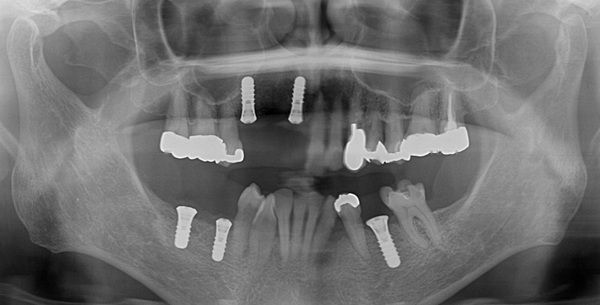

こちらがインプラント終了後のレントゲン写真になります。

無事に計画通り5本のインプラントが入りました。